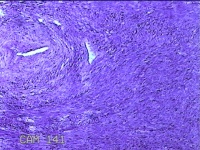

子宫肌瘤

性别

女

年龄

38岁

临床诊断

一般病史

发现子宫肌瘤复发7年余。

标本名称

大体所见

灰白粉红色结节样肿物8.5x5.5x4cm一个,表面糜烂,切面灰白色,编织状,质中。

富于细胞性平滑肌瘤

考虑富细胞平滑肌瘤。

组织处理和染色都不太理想。